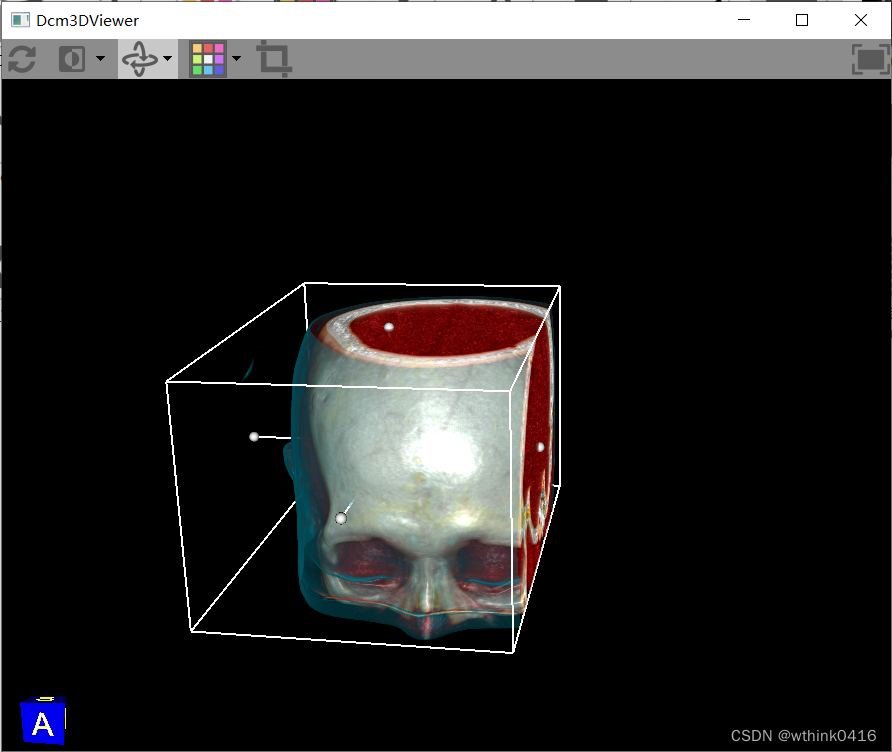

12、点击![]() 3D图标后,弹出三维重建窗口,该窗口为独立窗口,可以同时选择其他序列进行三维重建,方便进行对比

3D图标后,弹出三维重建窗口,该窗口为独立窗口,可以同时选择其他序列进行三维重建,方便进行对比

16、点击![]() 裁剪图标,弹出包围盒,进行裁剪操作

裁剪图标,弹出包围盒,进行裁剪操作